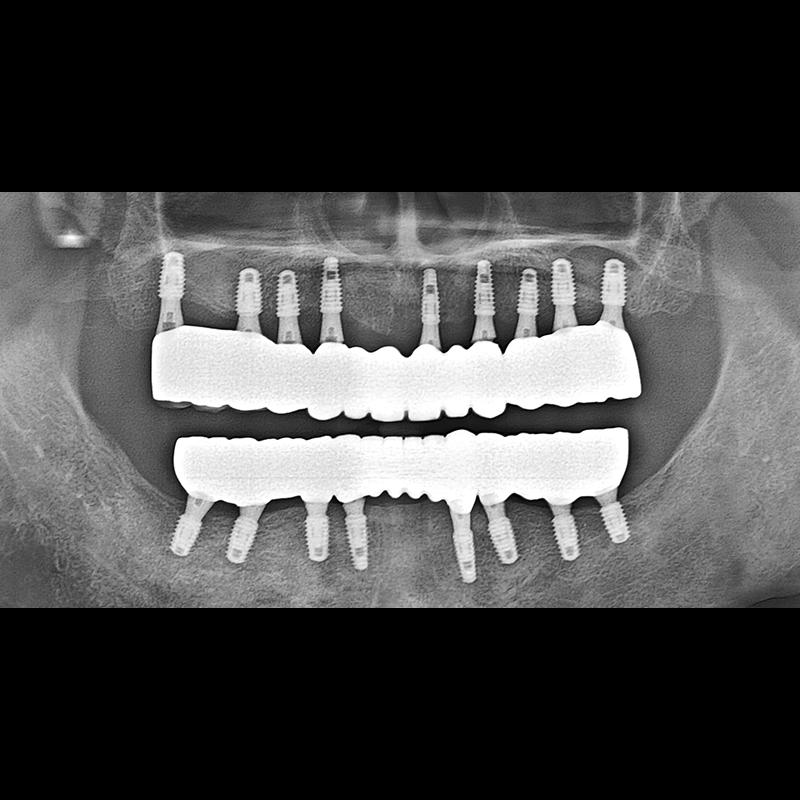

BEFORE AFTER

임플란트 전후사진 2025.05.30

결손된 치아 부분과 살리기 힘든 치아 위치에 임플란트를 식립하였습니다.